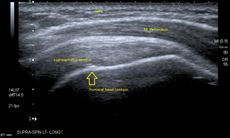

الموجات فوق الصوتية